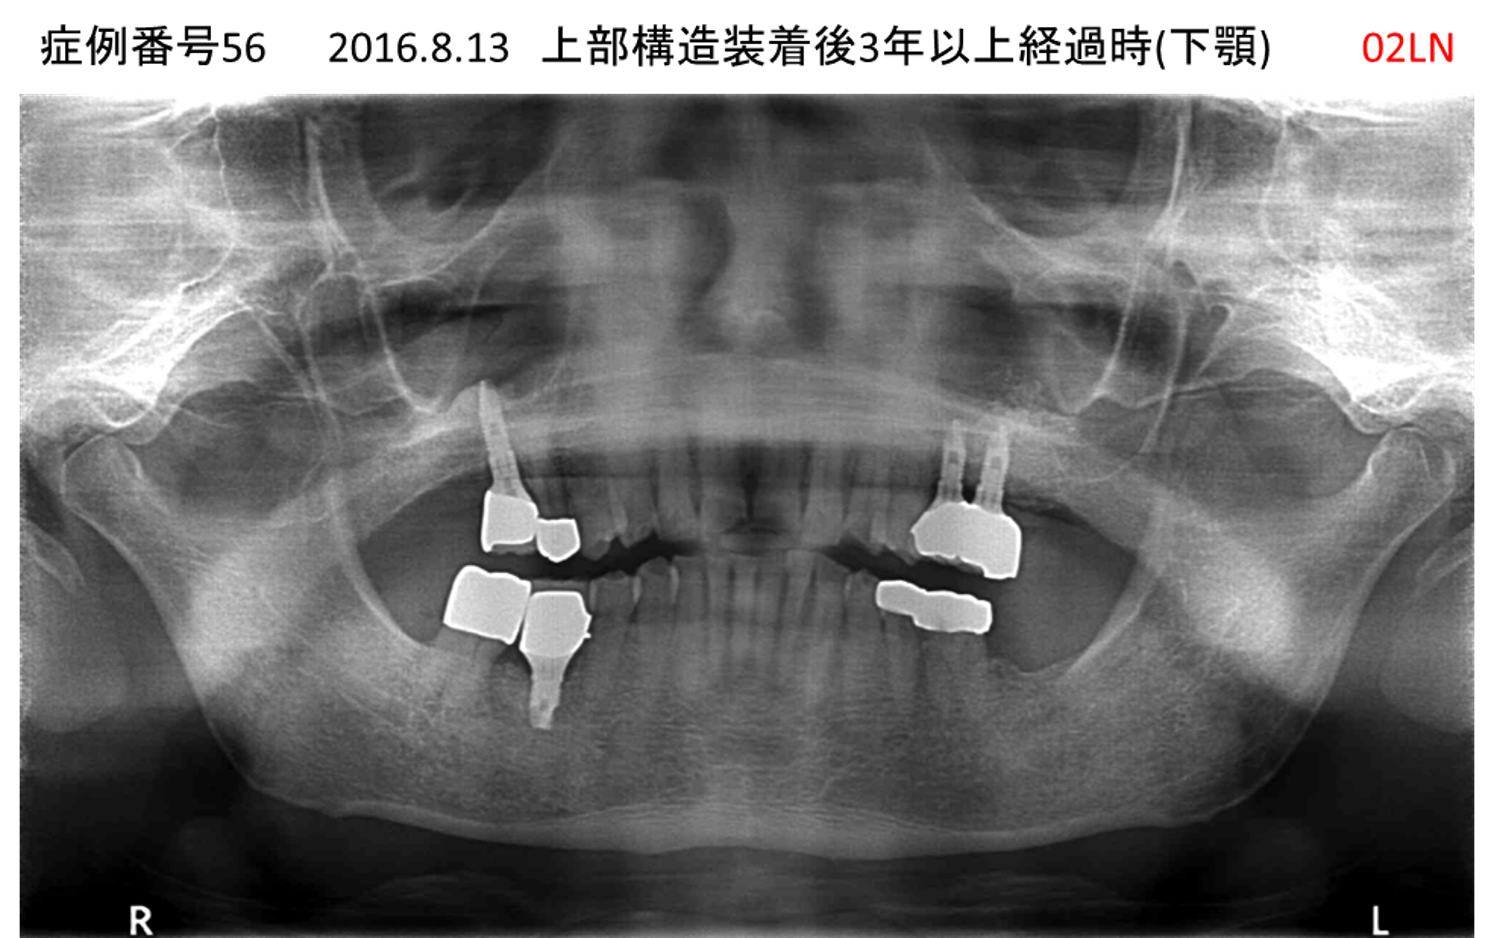

義歯が合わない、噛めない患者様のインプラント症例

| 治療名称 |

インプラントコーヌステレスコープ |

| 治療費用 |

270万円+税 |

| 治療期間 |

4か月 |

| 患者さんの症状(主訴) |

義歯が合わない、噛めない |

| 治療内容 |

インプラント、義歯作製(コーヌステレスコープ) |

| 治療結果 |

しっかり噛めるようになった。見栄えが良くなった。 |

| 治療の注意点(リスク/副作用) |

義歯が壊れた場合、インプラントが壊れた場合は再治療が必要 |